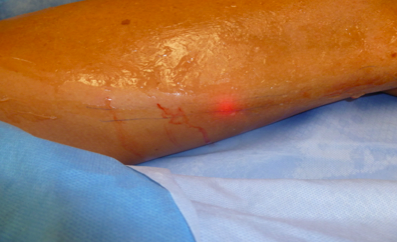

The leg is prepped with antiseptic and surgically draped.

A sheath (fine tube) is placed in the vein with the aid of ultrasound. The laser fibre is then introduced into the vein and carefully positioned.

Further local anaesthetic ensures good contact between the laser fibre and the vein.

Laser Treatment of the vein is then performed. Pulses of laser energy pass from the tip of the fibre to the vein, causing it to close as the fibre is gradually moved along the vein. When complete the fibre is removed.